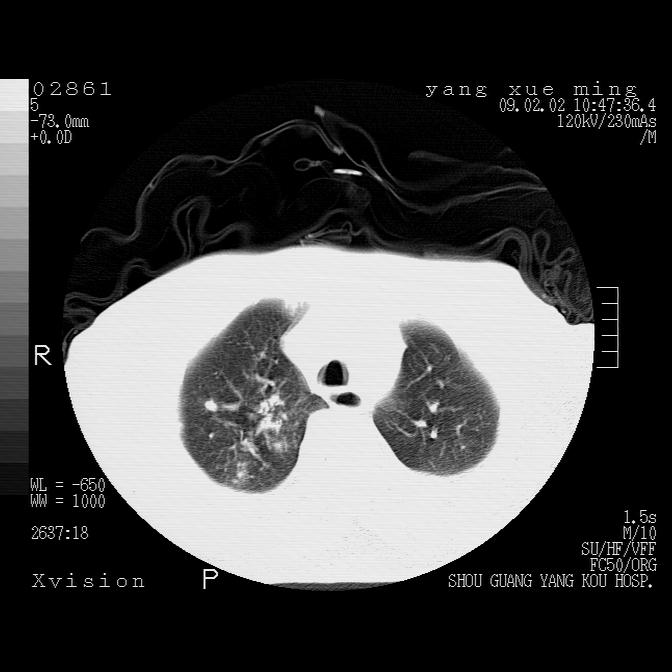

以下是引用lkc8963在2009-2-3 20:11:00的发言:[br]1)右上肺陈旧病灶。2)右下肺团块及团片影,影像表现符合感染。3)左心增大,左冠脉钙化,符合冠心病。4)双侧肺门扩大,以左侧为著,肺动脉干略粗,左上肺局限性气肿,为谨慎起见,需除肿瘤,建议增强。

以下是引用zbp537在2009-2-3 19:08:00的发言:[br]我诊断为肺泡性肺水肿。[br]诊断依据:[br]1、心影普遍增大,肺血管增粗,并见絮状高密度影,肺门改变显著。[br]2、临床上表现胸闷咳嗽,无发烧,不是一个典型的肺部感染的病史。